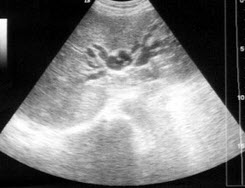

某患者右肾区疼痛数日,体温38℃。根据该患者右肾声像图表现,最可能的超声诊断为()

A.肾周围炎

B.肾炎

C.肾结石

D.肾结核

E.肾周血肿